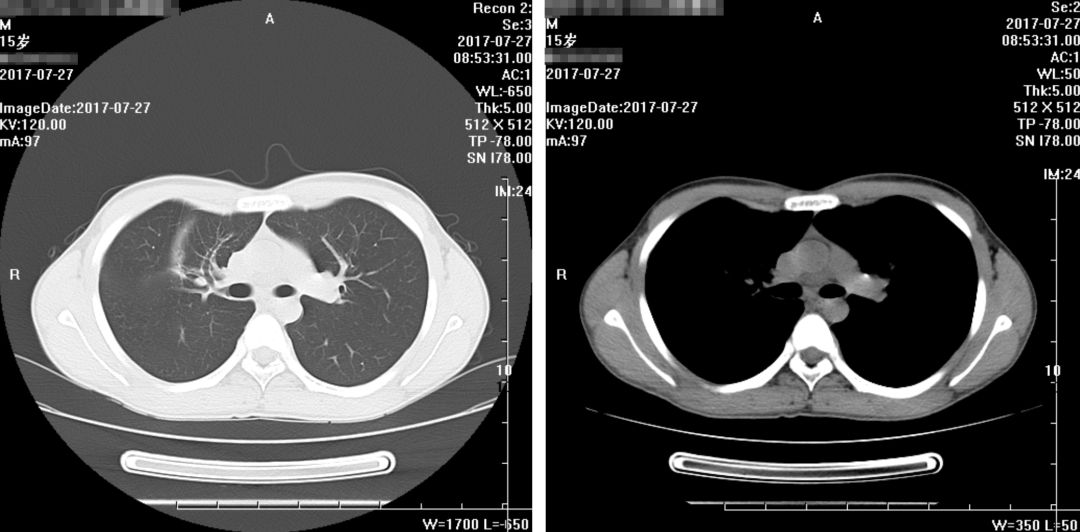

出院之后,家属不放心,又在门诊陆续复查了几次,且看患者恢复情况:

(2017年7月27日)

(2017年12月28日)